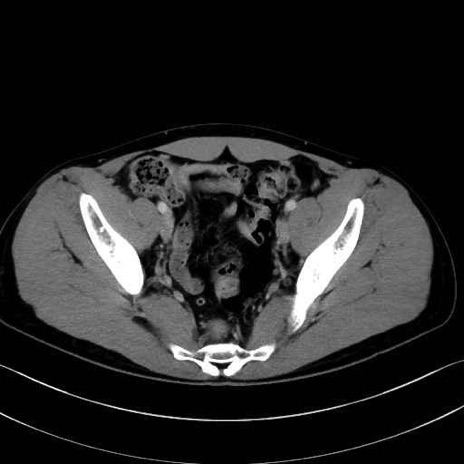

精嚢(seminal vesicle)のCT画像における解剖

症例

【症例】20歳代 男性 スクリーニング